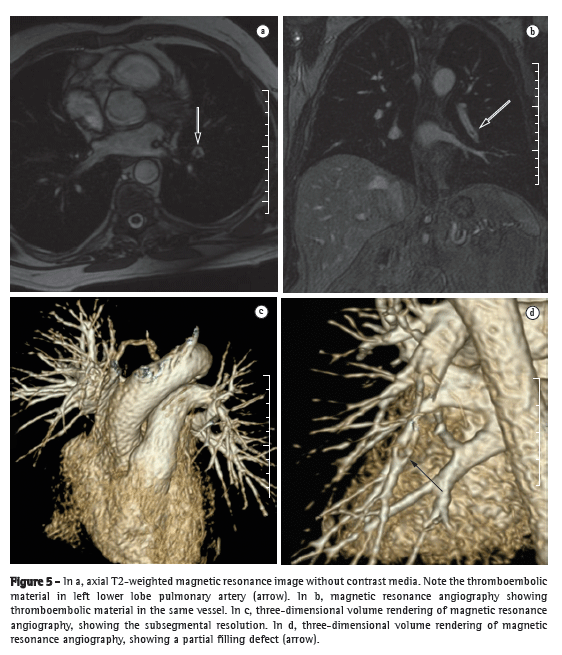

After the initiation of treatment, patients should be reevaluated, generally every 3-4 months, through analysis of the symptoms, physical examination findings, 6MWD, and BNP levels, in order to assess the response to treatment and decide the course of action. In localities where the 6MWT cannot be performed in a corridor, functional evaluation can be performed by means of a treadmill 6MWT, a protocol that has previously been validated for use in patients with PH.(54) If patients present clinical improvement or stabilization, as well as improvement or stabilization of the aforementioned markers, the treatment should be maintained; otherwise, an investigation should be performed in order to find the cause of treatment failure and avoid clinical deterioration. Infection, dietary noncompliance (excessive ingestion of salt or fluids), or the inappropriate use of the drugs are common causes of decompensation. If an evident cause is not found, a new hemodynamic evaluation can be performed, and, if hemodynamic worsening is confirmed, the specific treatment should be optimized by increasing the dose or adding another class of drugs. Patients who present with progressive worsening despite the optimized clinical treatment should be referred for an evaluation for lung transplantation (Figure 5).(55)